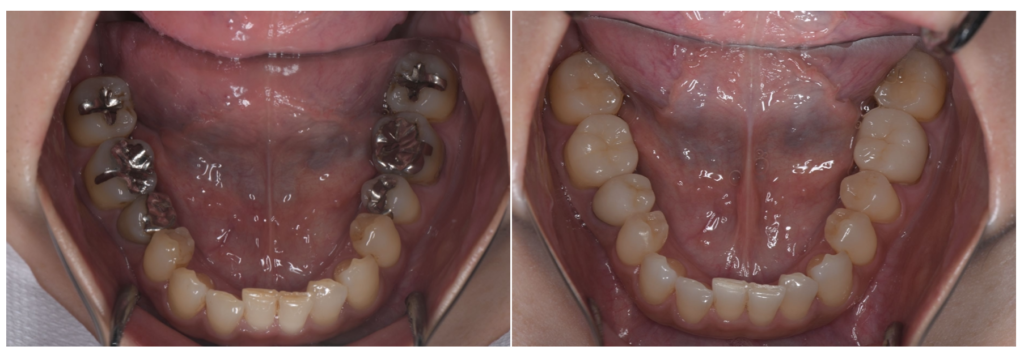

銀歯を白くする治療で失敗しないために──“接着”と“噛み合わせ”が運命を決める理由

「銀歯を白くしたい」「口を開けたときに金属が見えるのが気になる」このようなお悩みからセラミック治療を検討される方は非常に多くいらっしゃいます。とくに40代以降の女性の患者さまは、見た目はもちろん、“健康面として歯を…